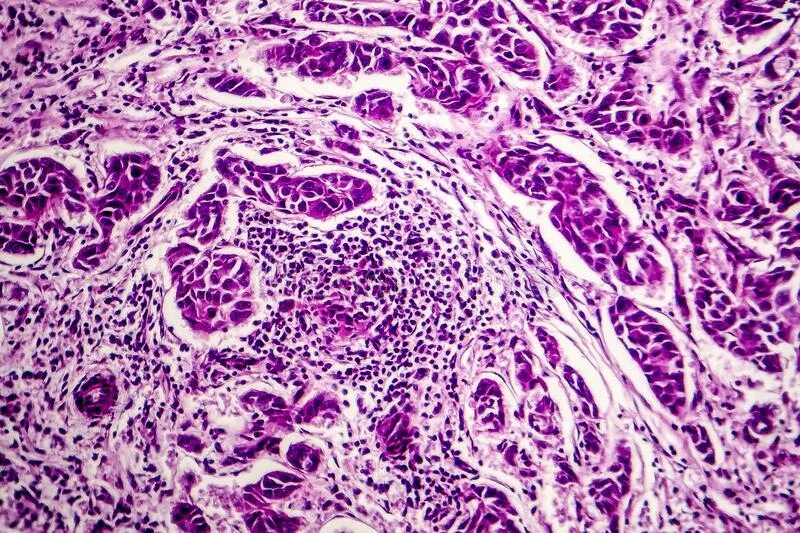

Метастазы в лимфоузлах легких